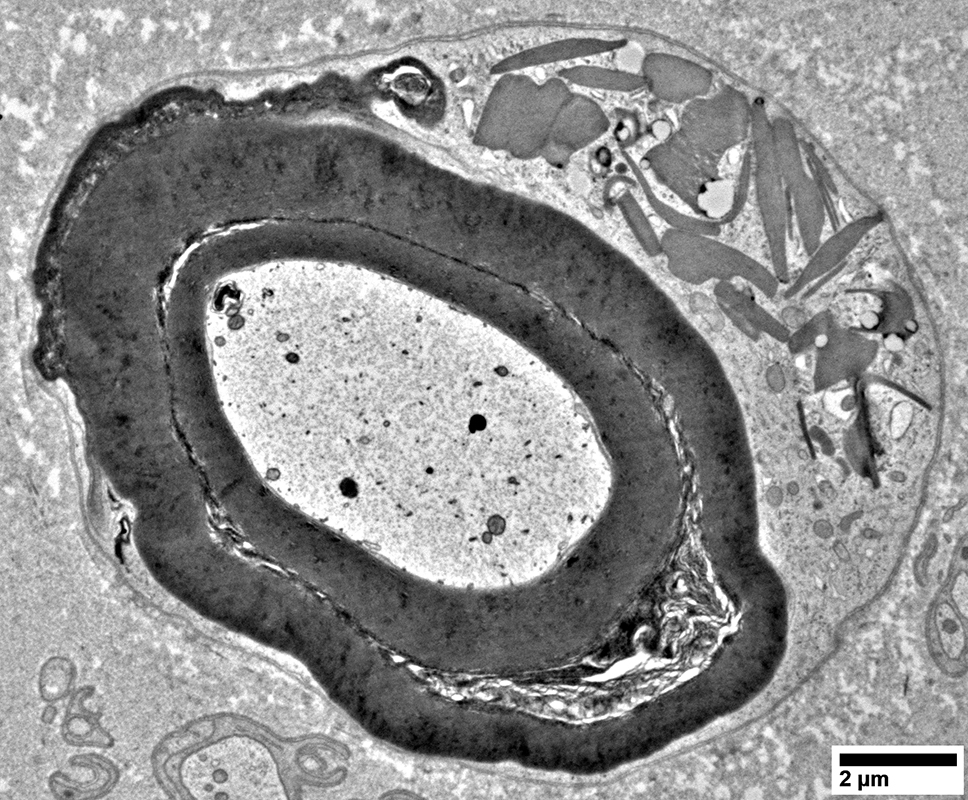

Lipid Droplets & Myelin debris segregated in different Schwann cell processes

From: R Schmidt